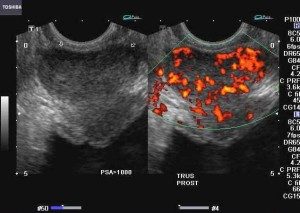

Carcinoma alla prostata: ricerca rivela come alcuni trattamenti riducono le dimensioni del pene

La prostatectomia, la rimozione chirurgica della prostata, l'intervento piu' comune nel caso di tumore della ghiandola, e' sostanzialmente inutile in...

l’Urologia dell’ Ospedale IRCCS Casa Sollievo della Sofferenza San Giovanni Rotondo - Foggia E’ ALL’AVANGUARDIA IN ITALIA CON INNOVATIVE TECNICHE...